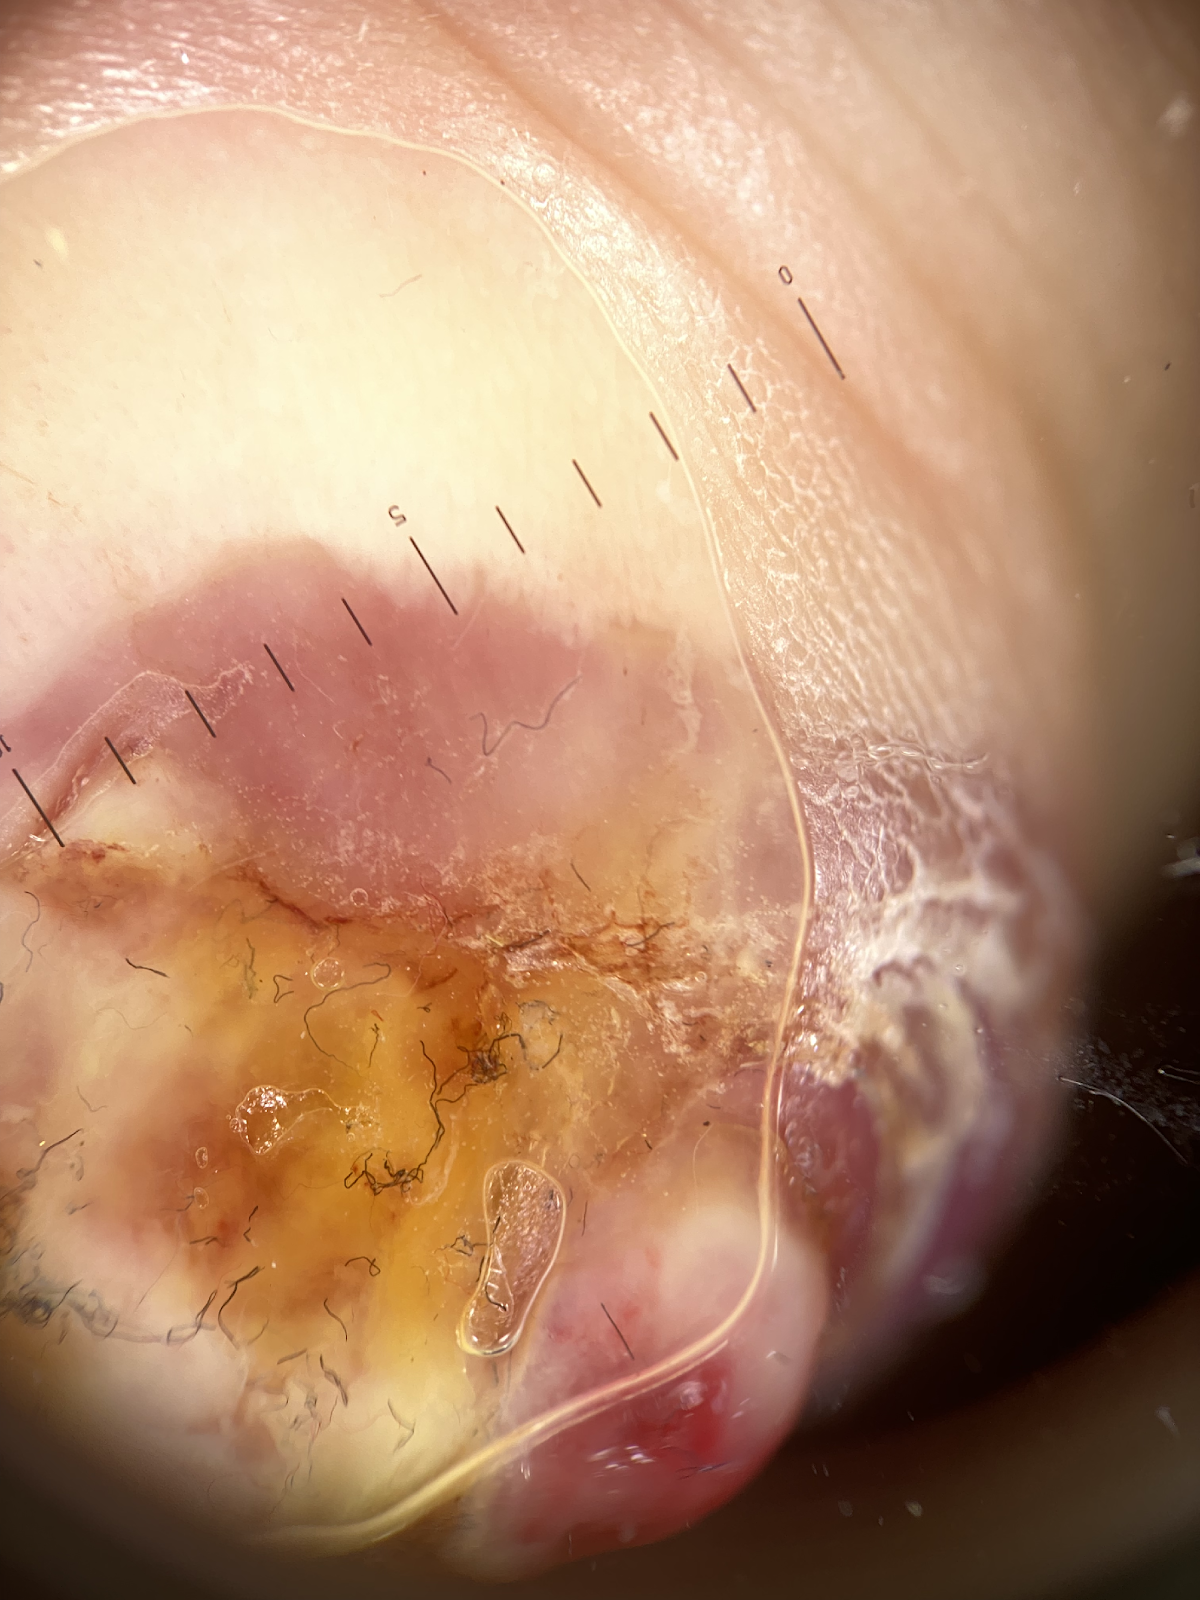

Am Fingerendglied des linken Zeigefingers imponiert ein etwa kirschgroßer, vulnerabel wirkender, glasiger rötlich-gelblicher Knoten. Das übrige Integument erscheint unauffällig. Insbesondere axillär links unauffälliger LKN-Status (Abb. 1).

Abb. 1: Patientin im 7. SSM (a). An der lateralen Endphalanx des Dig. II links findet sich ein maximal 2 cm durchmessender glasig glänzender, fibrinös belegter, teils hämorrhagisch tingierter, teils rund und breit aufsitzender Exophyt (b-d). Die Umgebung ist moderat gerötet. Der obere Anteil wird von der noch intakten Epidermis kragenartig umschlossen (e,f). Dermatoskopisch ist eine ausgeprägte Vaskularisiation mit Hämorrhagien auffällig. Daneben findet sich auch eine Impetiginisierung (g,h).